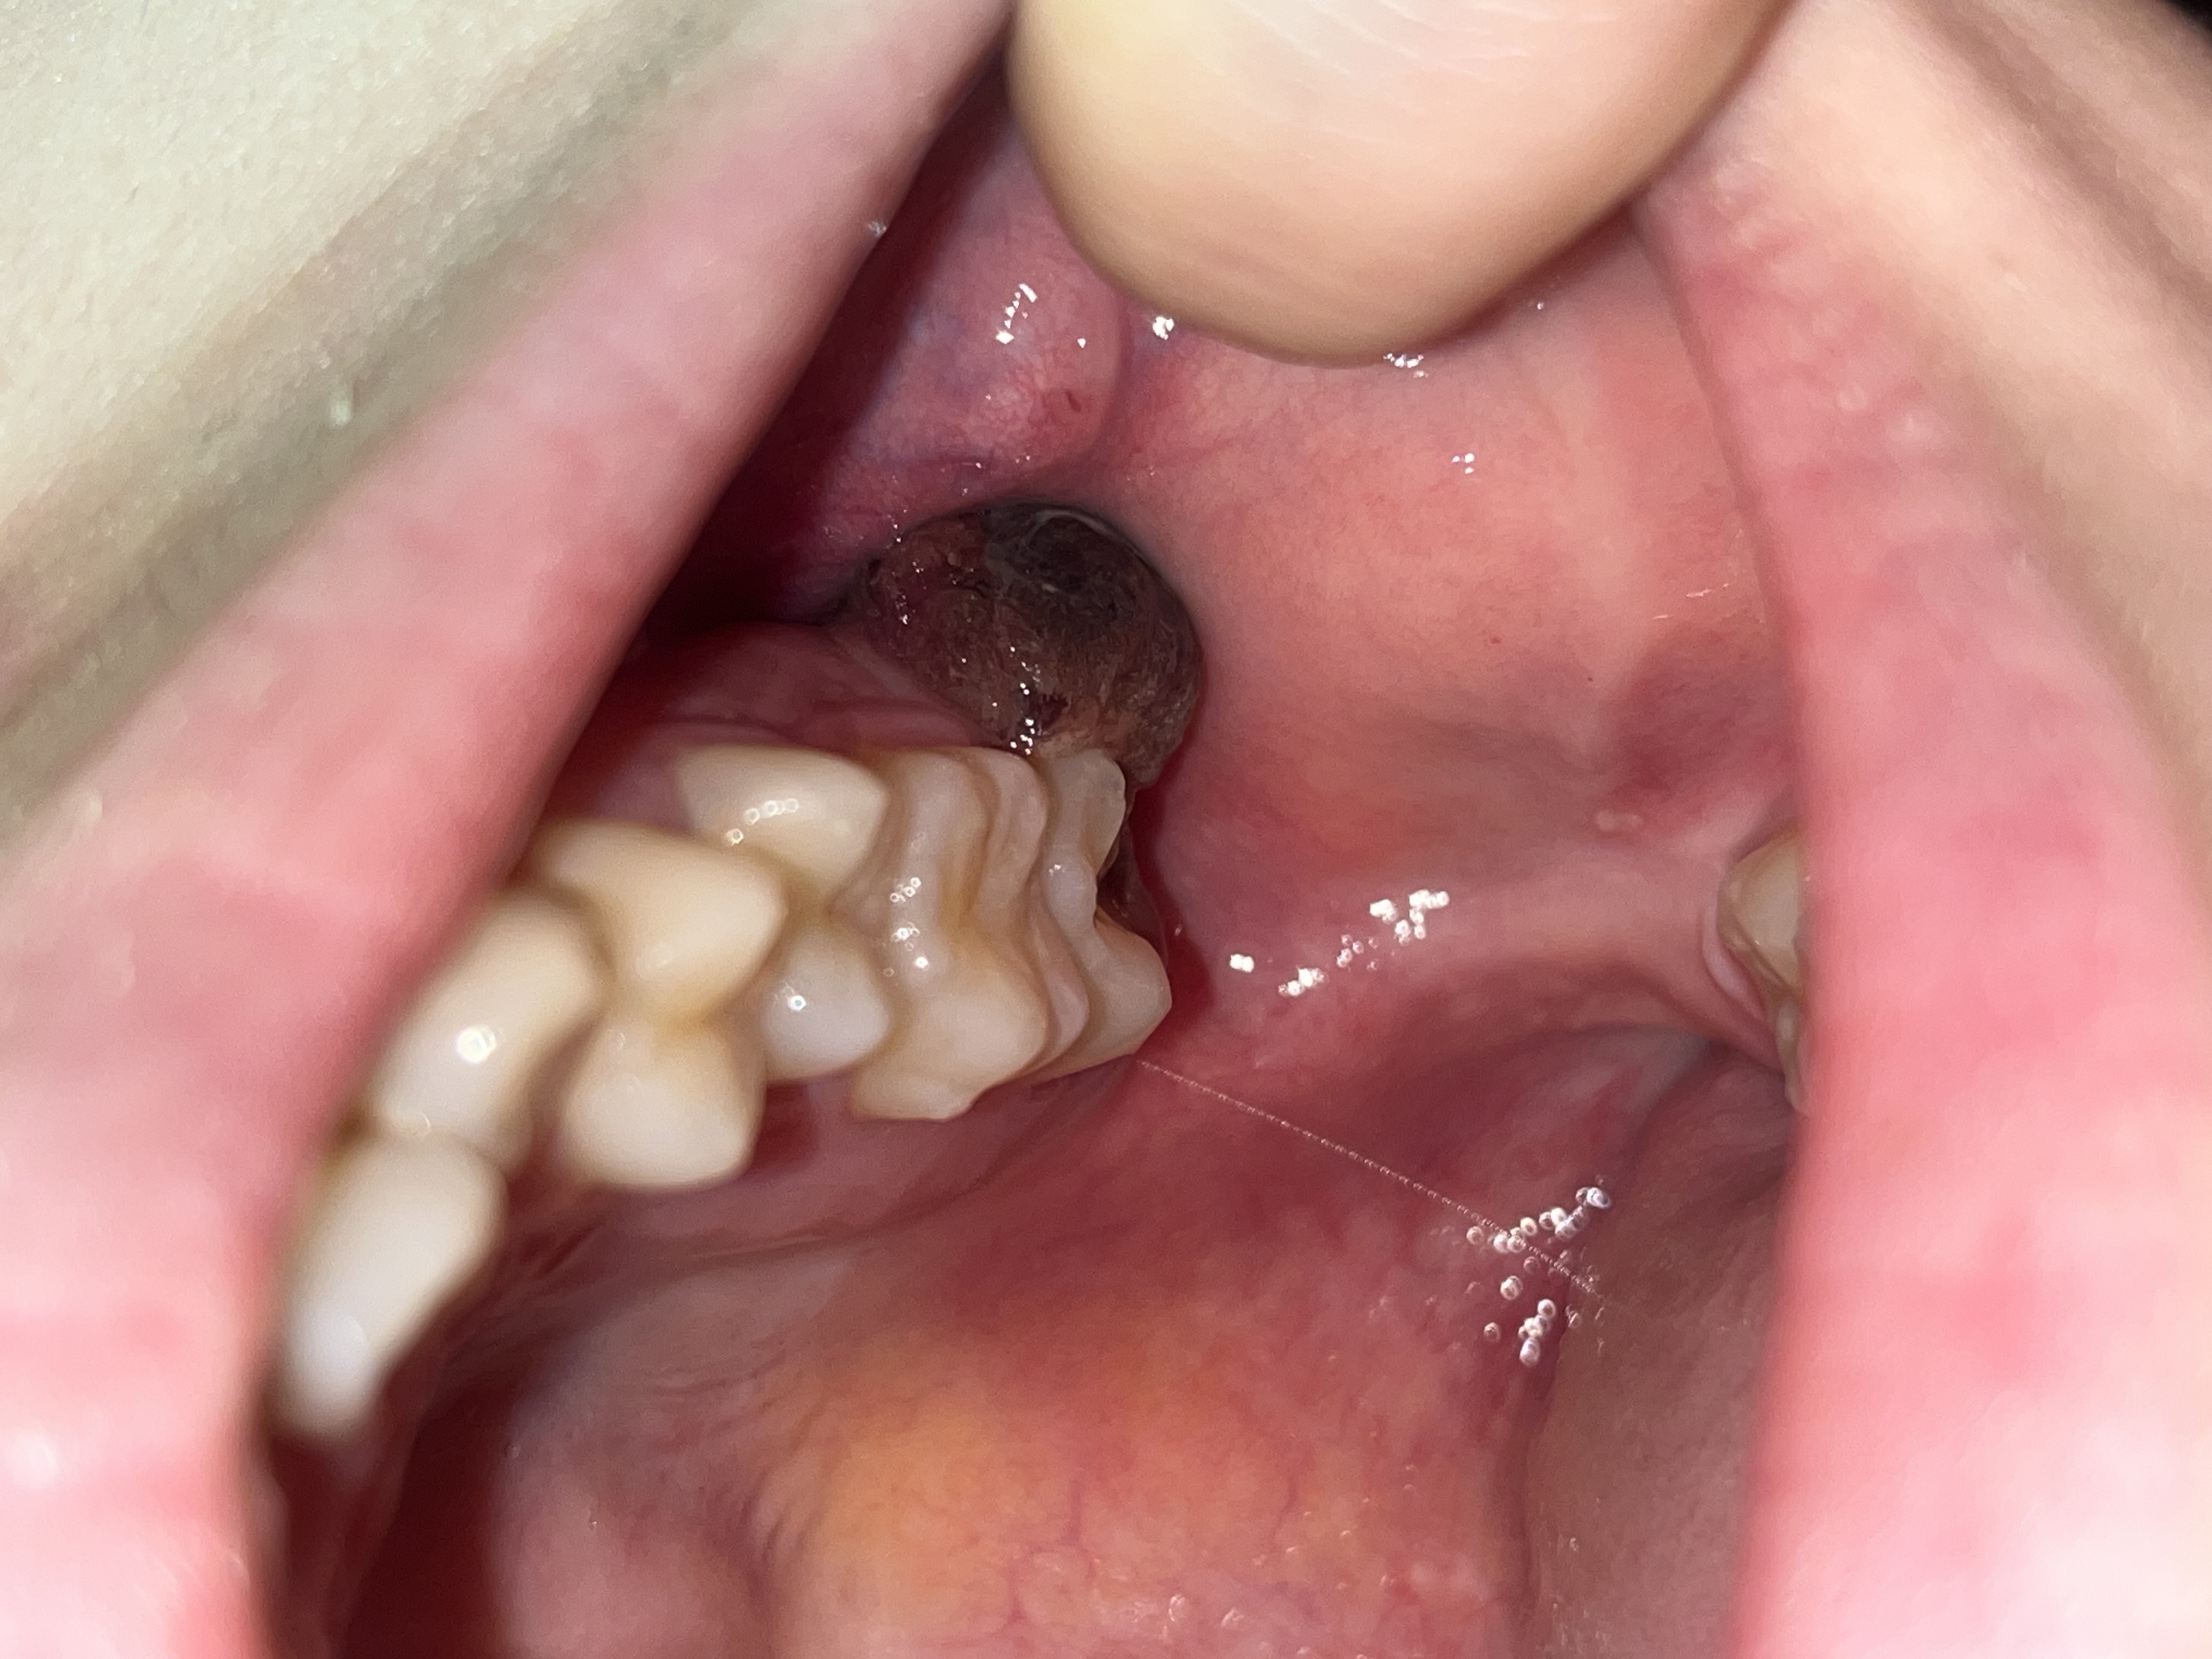

親知らず抜歯後、大きな血餅が出来ました。取れたらドライソケットになりますか?

血餅は調べて知りましたが、穴の開いた箇所だけというより、歯がもう一つついているくらいの大きい?血餅が両サイドにできています。

大きくて取れそうで不安です。

万が一取れてしまったらドライソケットというものになるのでしょうか。

あふれている部分が取れても問題ありません。

くぼみに残っていれば大丈夫です。

ごっそり取れてくぼみの中に血餅が全くなくなり、痛みが強く出るというのがドライソケットですが、上の歯でそうなる確率はかなり低いです。